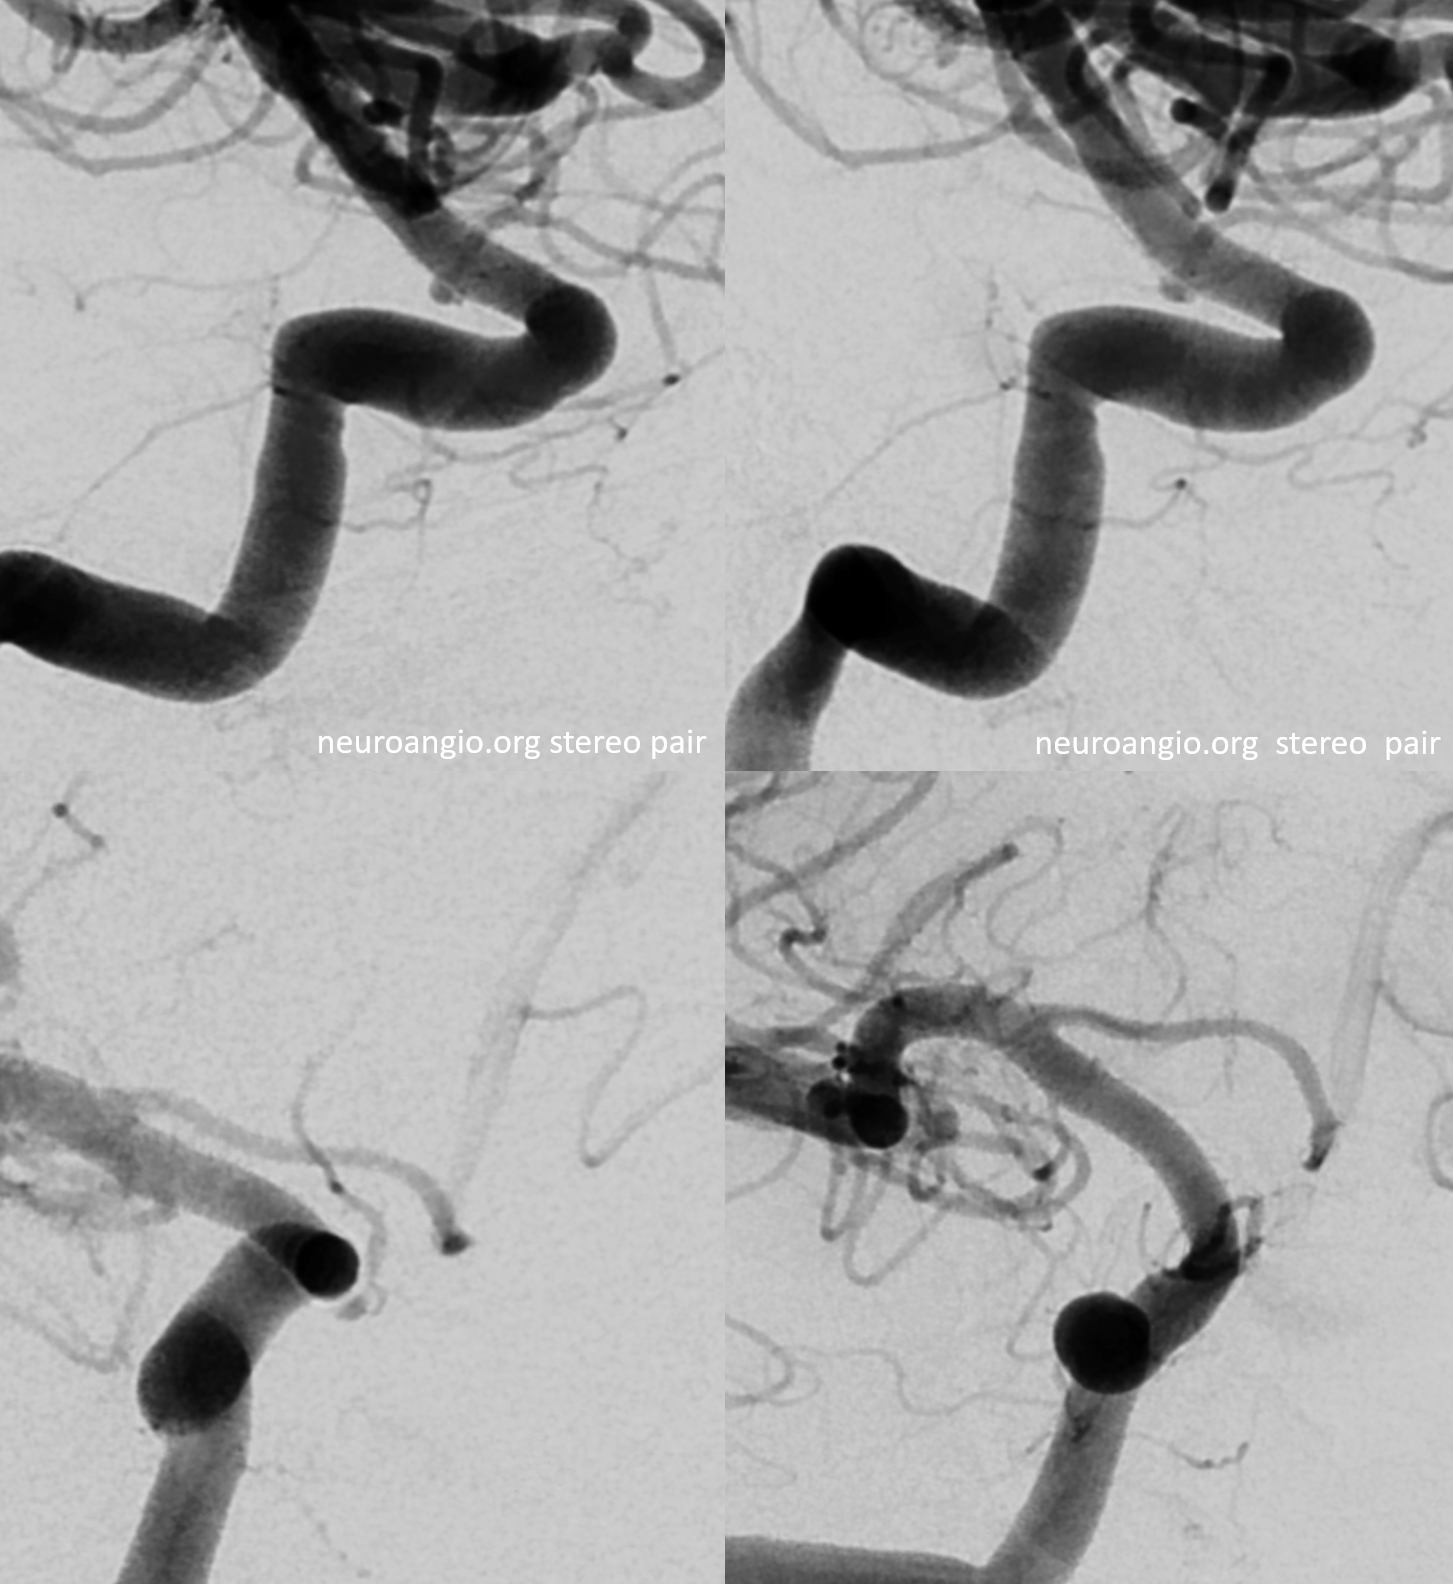

Stereos and MIPs. Both superior and inferior hypophyseals are well seen. The superior hypophyseal, despite being invisible on standard issue views, is quite large, even having two branches to the hypophysis.

Cross eye stereo

Cross-eye stereo

Another Infundibulum here –stereo

There is a very real small ophthalmic aneurysm though…

Also see small PCOM contributing to chiasm / tract supply (arrows). A large superior hypophyseal supplies the stalk. The inferior hypophyseal / MHT are hypoplastic